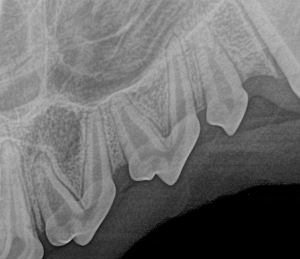

Feline Full Mouth Radiograph example